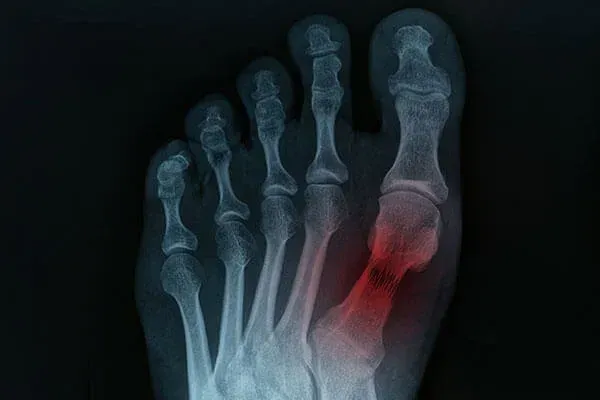

Stress fractures are small cracks in bones that often stem from repetitive motions. Stress fractures are common injuries among athletes, runners, or individuals with weakened bones due to poor nutrition or medical conditions. Symptoms of stress fractures include enduring pain during physical activity, tenderness, and mild swelling that primarily occurs in the lower leg and foot. Diagnosis of stress fractures can be elusive as an X-ray may be unable to detect the hairline cracks in the bones. In those cases, a podiatrist can employ an MRI or a bone scan for confirmation. Treatment typically entails rest, immobilization using casts or braces, and, in rare instances, surgery. Early detection and intervention can help to avert further complications and ensure a smoother recovery process. If you believe you may have developed stress fractures in your feet, it is suggested that you make an appointment with a podiatrist for thorough testing and treatment options.

Stress fractures are the result of repetitive force being placed on the bone. Since the lower leg and feet often carry most of the body’s weight, stress fractures are likely to occur in these areas. If you rush into a new exercise, you are more likely to develop a stress fracture since you are starting too much, too soon. Pain resulting from stress fractures may go unnoticed at first, however it may start to worsen over time.

Stress fractures do not always heal properly, so it is important that you seek help from a podiatrist if you suspect you may have one. Ignoring your stress fracture may cause it to worsen, and you may develop chronic pain as well as additional fractures.